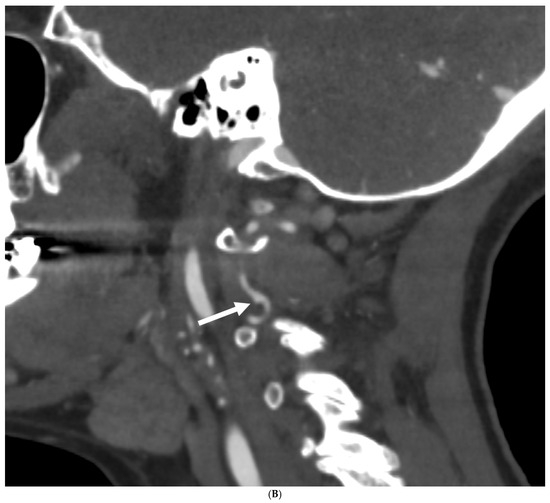

Prevalence of Intracranial and Cervical Artery Abnormalities in Patients with Hypermobile Ehlers–Danlos Syndrome and Hypermobility Spectrum Disorders Presenting to an Academic Headache Clinic

by Todd D. Rozen, Katelyn A. Bruno, Ethan M. Rozen, Frances C. Wilson, Marysia S. Tweet, Raymond C. Shields, Sharonne N. Hayes, Dacre R. T. Knight, Shilpa N. Gajarawala, Sukhwinder J. S. Sandhu, Alok A. Bhatt and DeLisa Fairweather

Neurol. Int. 2026, 18(2), 33; https://doi.org/10.3390/neurolint18020033 - 11 Feb 2026

Background/Objective: It remains unknown whether patients with the more common forms of hypermobility carry an elevated risk for the development of intracranial/cervical artery abnormalities. The objective of this study was to determine the prevalence of unruptured intracranial aneurysms, spontaneous cervical artery dissections, and fibromuscular dysplasia in patients with hypermobile Ehlers–Danlos Syndrome (hEDS) and hypermobility spectrum disorders (HSD) who presented to an academic headache clinic. Methods: This is a retrospective cohort study. We used an electronic medical record to look for all patients seen at the Mayo Clinic Florida Headache Center and EDS Clinic between 2019 and 2025 with a diagnosis of hEDS or HSD and neuroimaging of both the intracranial and cervical arteries. Results: There were 103 patients who met the inclusion criteria. There was no statistically significant difference between hEDS and HSD patients in developing cerebral/cervical arterial anomalies. Of the sample, 95% of the hypermobile patients with abnormal neuroimaging also had migraine. A total of eleven (10.7%) patients (hEDS + HSD) were diagnosed with unruptured intracranial aneurysms. Trends included age less than 50 years, small aneurysms in the anterior circulation, and having migraine with aura. Five (4.8%) patients were diagnosed with spontaneous cervical artery dissection with trends for HSD, over the age of 50 years, vertebral artery involvement and a history of migraine without aura. Six (5.8%) patients were diagnosed with fibromuscular dysplasia with trends for HSD, over the age of 50 years, carotid artery involvement and a history of migraine with aura. Conclusions: This is the first study to identify that patients with the more common type of EDS, HSD and hEDS, and a possible concomitant history of migraine have a heightened risk for the development of unruptured intracranial aneurysms, spontaneous cervical artery dissections, and fibromuscular dysplasia. Our findings suggest the need for targeted screening with intracranial and extracranial arterial imaging for this unique patient population. Full article